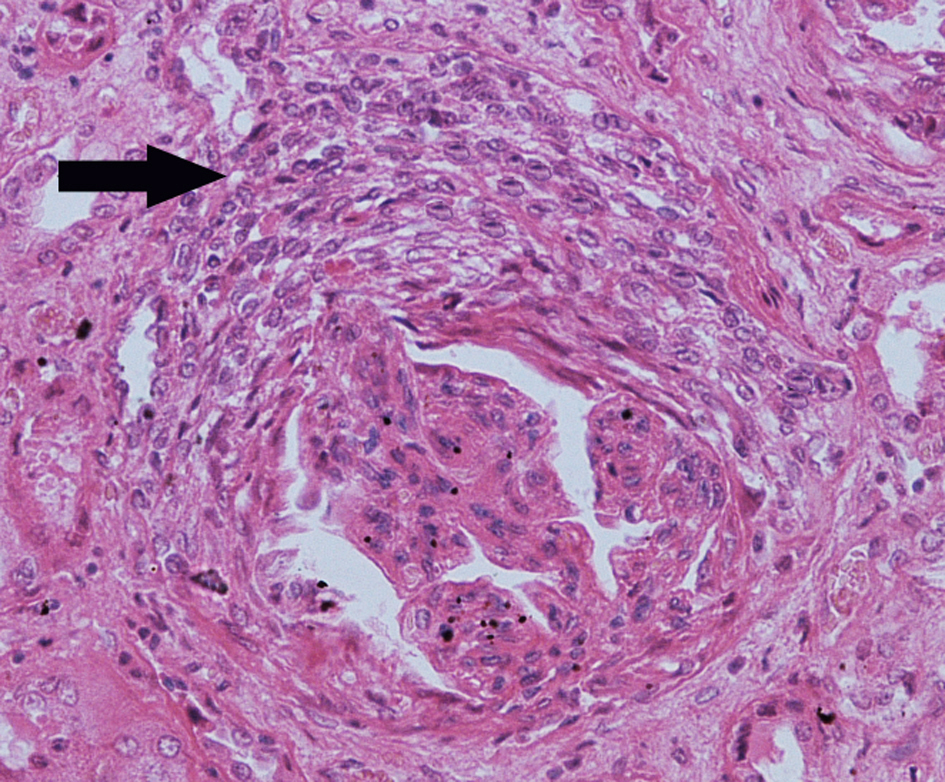

2.新月体性肾炎